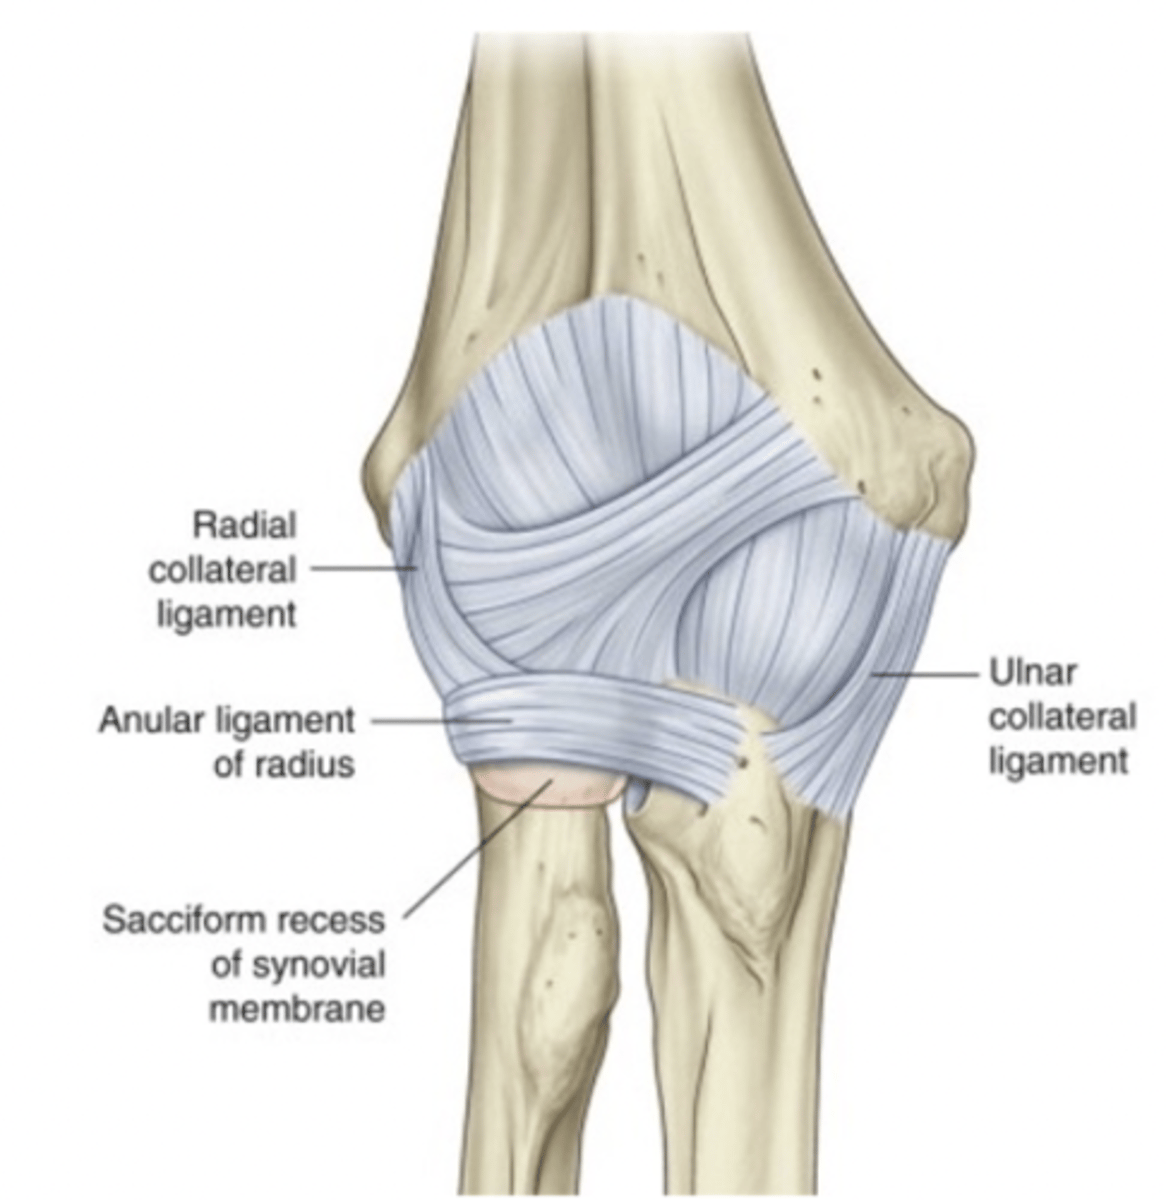

LCLC is a primary constraint to varus forces

1. lateral / radial collateral ligament (LCL or RCL)

- from lateral epicondyle to annular ligament

2. annular ligament (AL)

- attaches to anterior & posterior margins radial notch

3. lateral ulnar collateral ligament LUCL)

- lateral epicondyle to supinator crest of ulna

- LUCL is the primary constraint to posterolateral rotary instability

Lateral collateral ligament complex